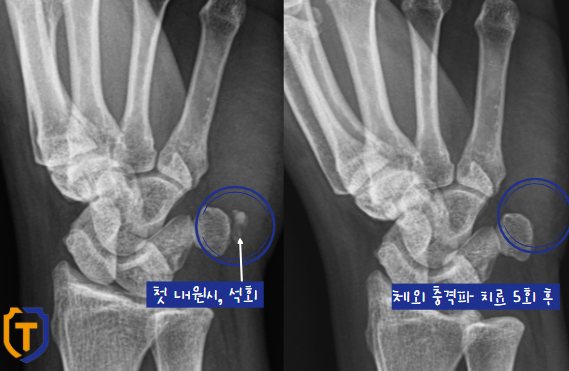

체외 충격파 후, 손목 경과

전, 후가 확연한 차이가 보이네요!